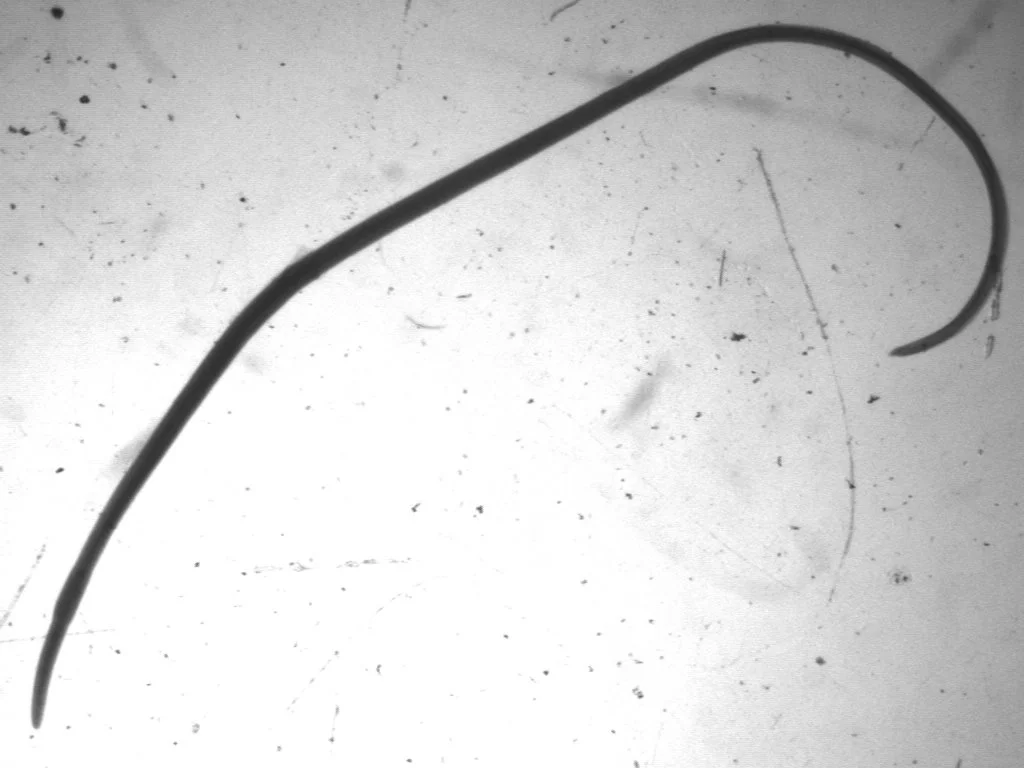

고래회충

고래회충이 의심될 때 병원에서 가장 먼저 해야 할 일은 바로 내시경이다. 위내시경을 보면 위벽에 머리를 박은 하얀 벌레가 보인다. 뉴스에선 이걸 ‘위벽을 뚫는다’고 표현했지만, 지나친 과장이다. 위벽을 뚫는 것과 머리를 살짝 묻는 건 엄연히 다르며, 실제로 위벽을 뚫고 복강으로 나간 고래회충은 아직까지 없다. 구덩이를 파려고 삽질을 하면서 “나 지금 지구를 뚫는 중이야!”라고 하는 사람은 없지 않은가? 그렇다면 “고래회충에 감염되면 약도 없다”는 말은 진짜일까? 약이 아예 안 듣는 건 아니겠지만, 원래 기생충의 유충은 성충보다 약에 대한 반응이 좀 떨어진다. 그렇다고 해도 약을 왕창 주면 제 아무리 고래회충 유충이라도 타격은 입을 것이다. 하지만 그렇게 하기보단 그냥 내시경으로 끄집어내는 편이 훨씬 더 신속하지 않겠는가? 그러니 ‘약도 없다’는 말보다 “내시경으로 쉽게 치료된다”라는 게 훨씬 더 정확한 표현이다. 복통 이외에도 고래회충의 유충에 대한 알레르기 반응이 생길 수 있는데, 원래 알레르기는 개인차가 있기 마련이다. 대부분은 별 일이 없지만 간혹 피부에 발진이나 두드러기가 생기거나 가려움증이 동반될 수 있다.